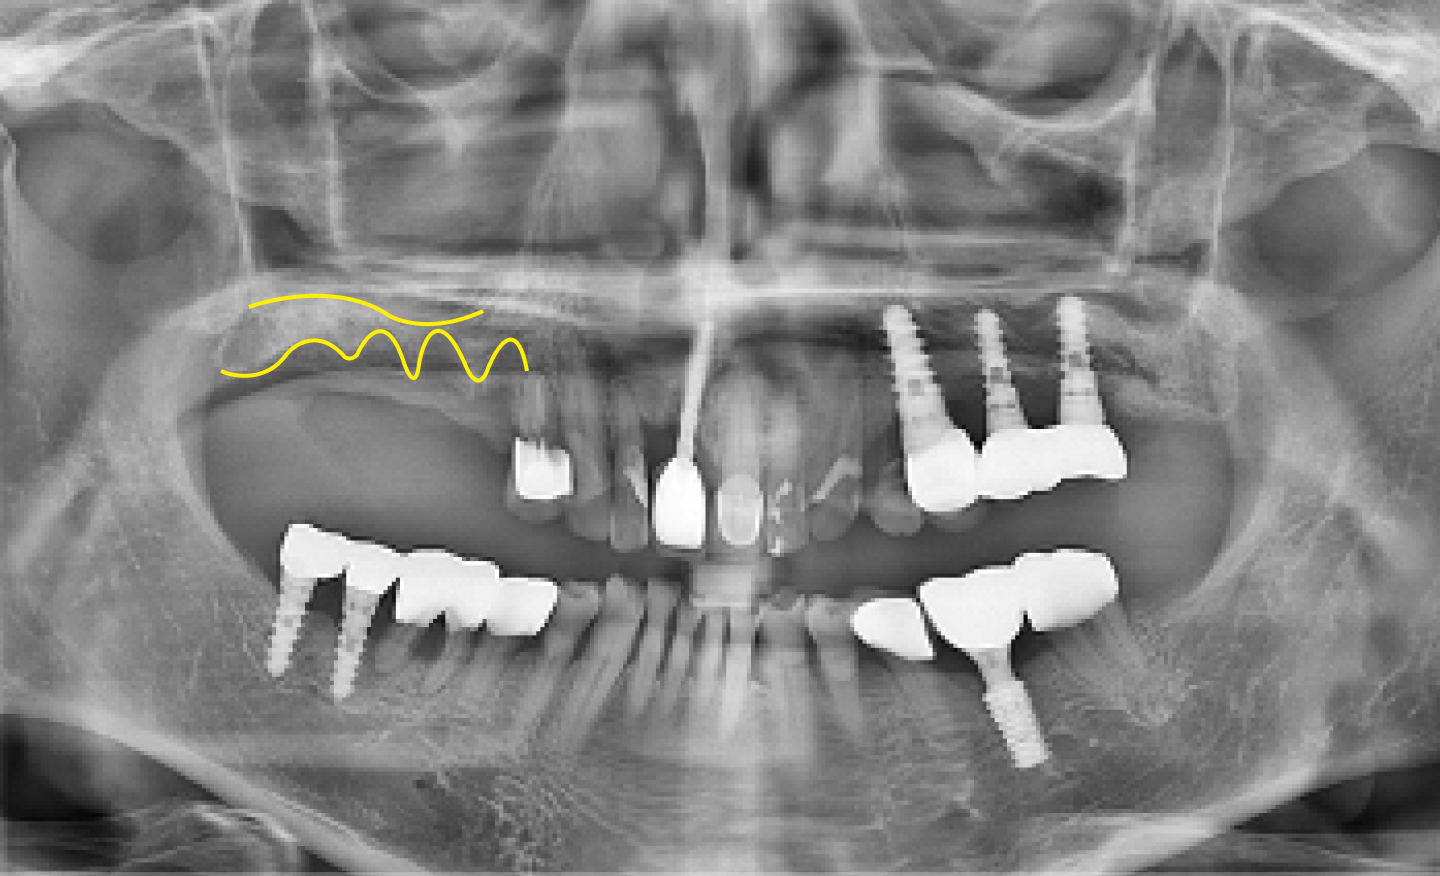

시흥치과 서울안심 전악 임플란트 즉시 임시치아 시술 후

AFTER

전악 임플란트 + 즉시 임시치아

*위의 이미지는 동일한 조건에서 촬영되었으며 별도의 보정 작업을 거치지 않았습니다.

*모든 치료과정에서 부작용이 발생할 수 있으므로 정확한 진단과 수술이 요구됩니다.